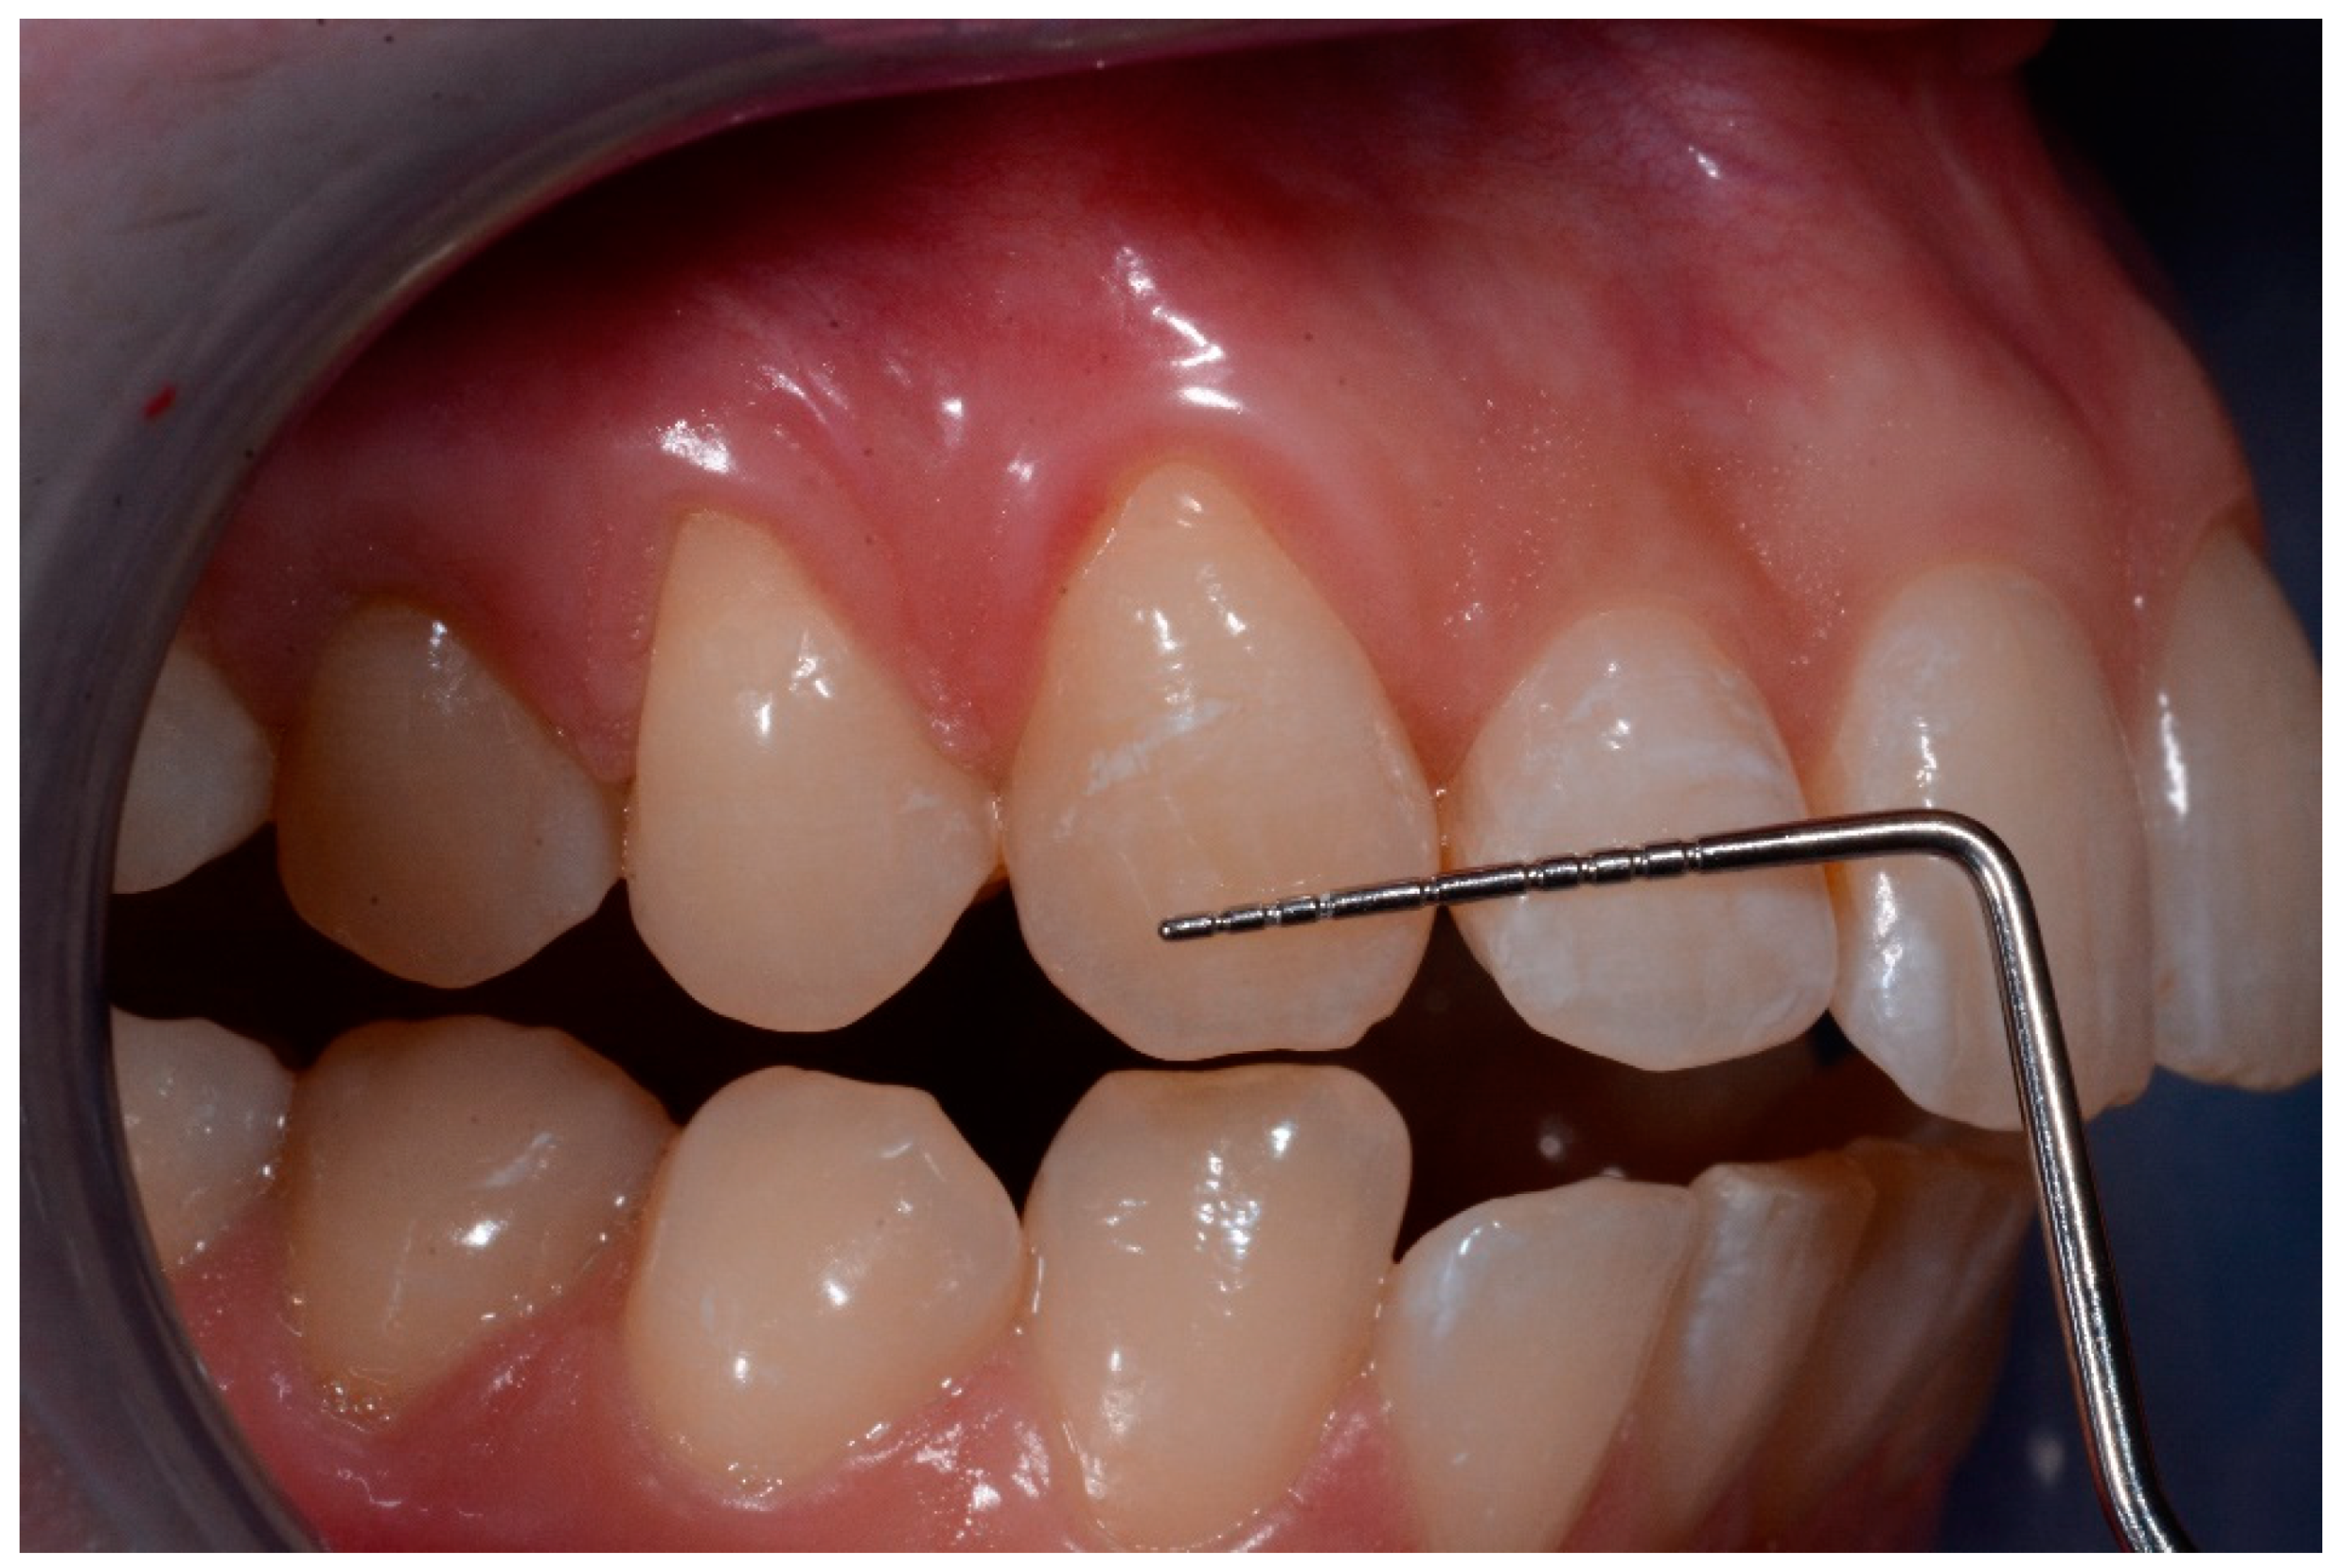

- The main dimension of lesions (mm)